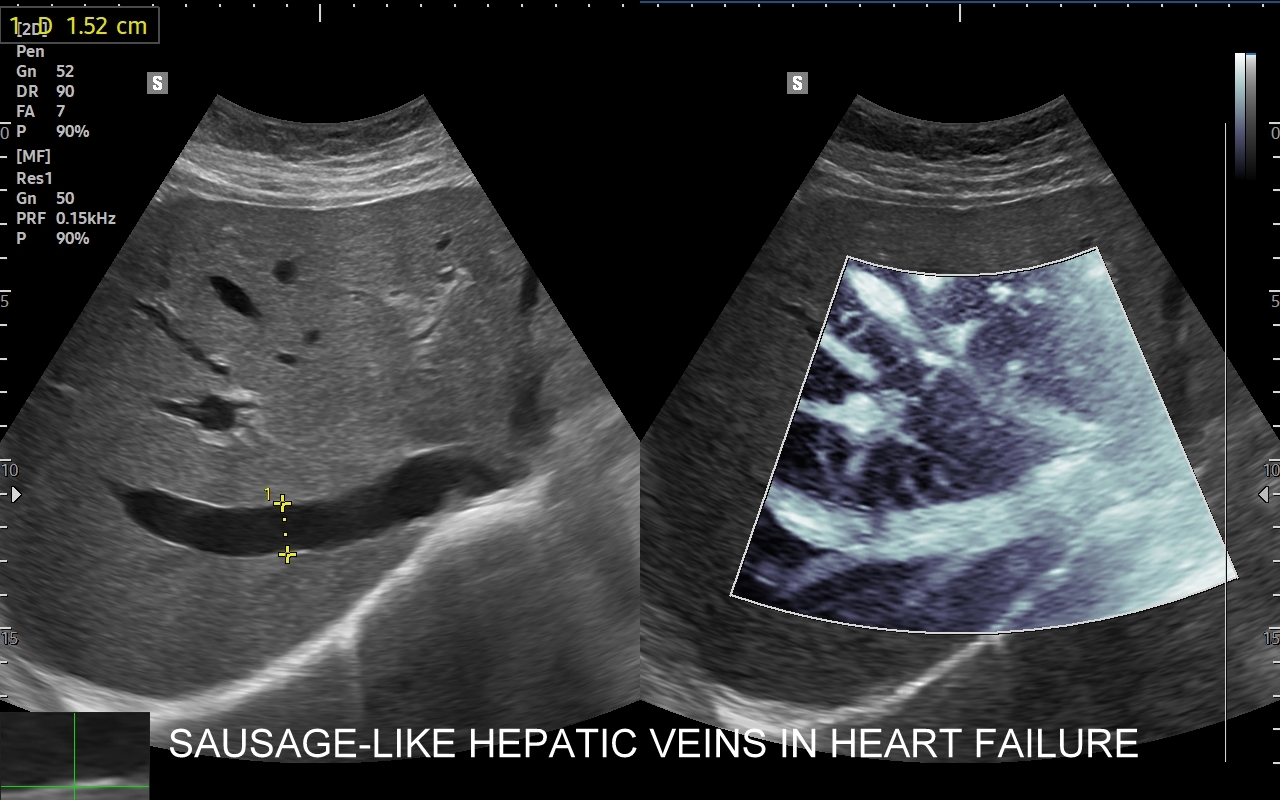

Badanie echokardiograficzne, nazywane także echo serca lub USG serca jest jedną z podstawowych metod diagnostyki kardiologicznej. W badaniu tym ocenia się zarówno morfologię narządu, jak i jego funkcję w postaci pomiarów wielkości jam serca, grubości mięśnia sercowego, czynności skurczowej oraz rozkurczowej lewej i prawej komory, oceny funkcji zastawek serca, wyglądu wsierdzia, osierdzia, a także w postaci pomiarów aorty, poszukiwania obecności patologicznych objawów sercowych związanych z chorobami innych narządów (np. choroby płuc, nadciśnienie tętnicze).

Wskazania do badania USG serca są bardzo szerokie i obejmują diagnostykę bólów w klatce piersiowej, przyczyn zmniejszonej tolerancji wysiłku, przewlekłego zmęczenia, duszności, obrzęków kończyn dolnych i wodobrzusza, ocenę powikłań nadciśnienia tętniczego i zawału serca, diagnostykę zaburzeń rytmu serca, zatorów tętniczych, udaru mózgu, diagnostykę przewlekłego kaszlu, utraty masy ciała, gorączki i powikłań anginy gardła w obrębie zastawek serca.

Specjalista chorób wewnętrznych z wieloletnią praktyką kardiologiczną i naczyniową. Szkolenie USG serca odbywał w Pododdziale Kardiodiagnostyki w Klinice Chirurgii Serca Akademii Medycznej we Wrocławiu. Jeden z najbardziej doświadczonych sonografistów w Polsce. Posiada ponad 25-letni staż kliniczny i szkoleniowy w Polsce oraz zagranicą (Wielka Brytania, Niemcy, Austria, Włochy). Wykonał ponad 40.000 badań USG. Wprowadził do rutynowego zastosowania w Polsce takie procedury diagnostyczne jak USG z kontrastem (CEUS) oraz multiparametryczne badania USG (MPUS). Certyfikowany lekarz Polskiego Towarzystwa Ultrasonograficznego z zakresu badań naczyniowych. Na co dzień dr Szczepański zajmuje się przeglądami zdrowia oraz specjalistyczną diagnostyką z zakresu chorób wewnętrznych i serca.